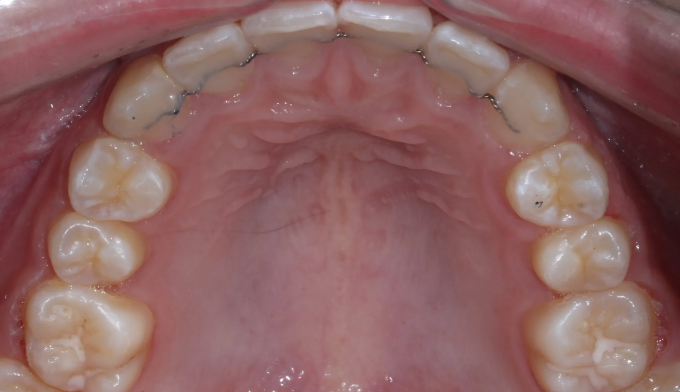

치아교정은 바른 교합을 형성하는것이 중요한 목적이기 때문에 윗니와 아랫니를 모두 교정하는것이 올바른 방법이지만, 특수한 경우에 있어서는 한쪽만 교정을 진행하는 경우도 있습니다.

위와 같은 경우는 환자 개인적인 사정으로 윗니만 교정한 경우입니다.

안모를 고려하여 앞니가 앞으로 뻗치지 않게 주의하면서 어금니만 후방이동시켜 송곳니가 맹출할 공간을 만듭니다.

총 교정기간은 13개월이 소요되었습니다.